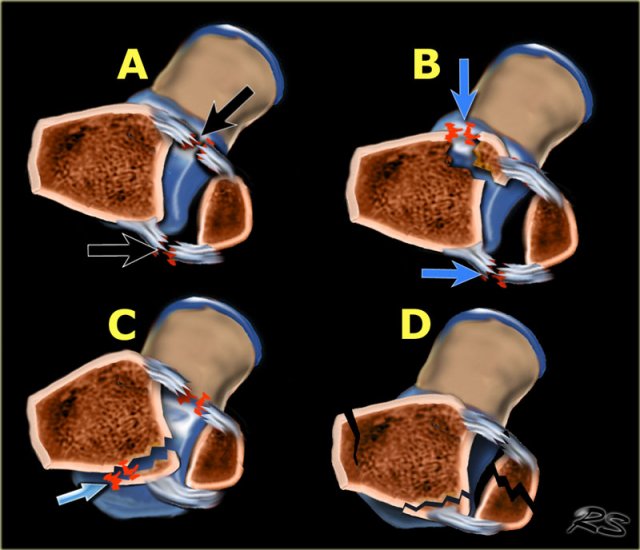

Ring of stability in the axial plane Ring of stability in the axial plane

There is also an ring of stability in the axial plane.

When the anterior and posterior syndesmosis rupture or avulse, then the ankle joint is also unstable.

There are many combinations of avulsion fractures and ligamentous ruptures that can produce an unstable ring in the axial plane.

A

Anteriorly the anterior syndesmosis is usually one of the first structures to rupture. When the posterior syndesmosis also ruptures, then the ankle is unstable.

B

Less commonly the anterior syndesmosis avulses from the tibial attachment - Tillaux fracture.

C

On the posterior side frequently the posterior malleolus avulses. Sometimes these fractures are difficult to detect, as we will discuss in a moment.

D

After the injury the bones frequently align again, which makes it difficult to detect.